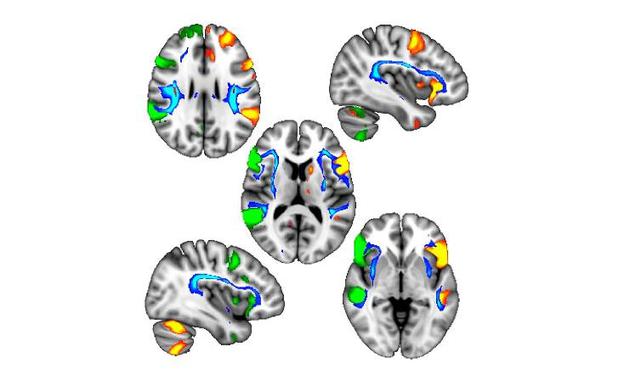

根据发表在《大脑》(Brain)期刊上的一篇论文,研究人员通过分析9000人的大脑成像,列出了一份基因突变的清单,这些基因突变会影响大脑两侧所发生的不同的大脑过程,反过来影响了对左手还是右手的偏好,还会影响一个人是否会患上某些神经系统疾病。

研究人员特别观察了721名左撇子和6685名右撇子的数据,包括大脑图像。分析显示,人类基因组中有4个位点与左利手有关,其中3个位点还与大脑发育有关,尤其是与语言有关的区域。左撇子人群的左、右脑语言区域以一种更协调的方式相互交流。